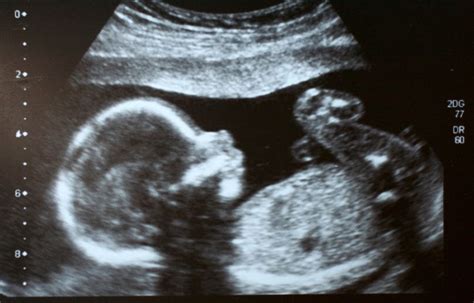

Pränataldiagnostik und Ultraschalluntersuchungen

Das Klinikum Oldenburg bietet detaillierte Ultraschalluntersuchungen während der Schwangerschaft, um wichtige Informationen über die regelrechte Entwicklung Ihres Kindes zu erhalten. Terminvereinbarung unter 0441/236-735 (Mo.-Fr.).

- 1. Umfassende Ultraschalluntersuchung: Bereits in früher Schwangerschaft erfolgt eine detaillierte Beurteilung der kindlichen Entwicklung.

- 2. Feindiagnostik im II. Trimester: Systematische Beurteilung aller darstellbaren Organsysteme und Strukturen des Kindes.

- 3. Fetale Echokardiographie: Spezielle Ultraschalluntersuchung des kindlichen Herzens, in der Regel im Rahmen der Feindiagnostik.

- 4. Doppler-Sonographie: Beurteilung der Blutflussverhältnisse im Körper des Kindes, in der Plazenta und in der Gebärmutter.

Die Abteilung für Ultraschalldiagnostik mit DEGUM-Stufe III und -Stufe II Ultraschall-Experten betreut werdende Mütter und ihre ungeborenen Kinder bis zur Geburt. (DEGUM-Stufen: Zertifizierung durch die Deutsche Gesellschaft für Ultraschall in der Medizin e. V.)

Erweiterte fetale Sonografie

Das Klinikum bietet auch eine erweiterte fetale Sonografie im II. Trimester an, um die Entwicklung des Kindes detailliert zu beurteilen.